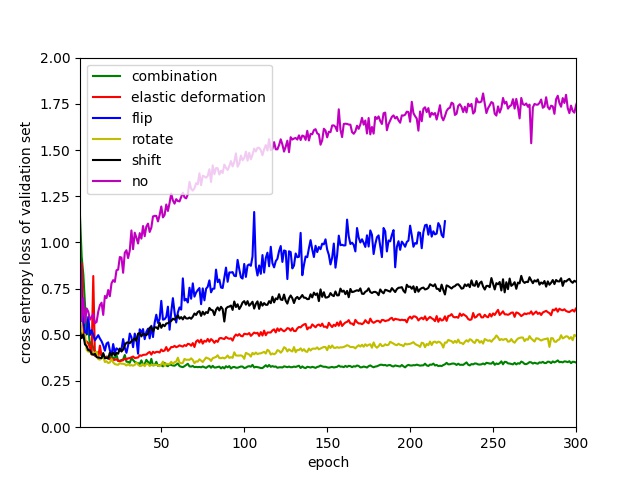

However, to the best of our knowledge, there is no systematic study of the effectiveness of these image transformation methods for nuclei segmentation using a fully convolutional network. We compare different training processes using rotation, flipping, shifting, rescaling and elastic deformation transform to augment the training data. To make fair comparisons, we let the training set and validation set have similar appearances by splitting each whole image into two sub-images and placing one in the training set and another one in the validation set. We randomly extract 6000 patches from the training set to train our neural networks and 6000 patches from the validation set for validation. The setting of these transformation methods is same with those reported in section II-C2. The comparison is shown in Fig.10(b). ’no’ means don’t apply data augmentation. ’combination’ means data augmentation is performed by combining elastic deformation, flip, rotate, shift and rescale. It is very clear that without data augmentation, the network has severe overfitting issue, validation loss starts to increase rapidly from epoch 5. Unexpectedly, rotating rather than elastic deformation has achieved the best performance in performance improvement. But only rotating operation still cannot prevent the overfitting. One has to combine all of these transform methods together to do data augumentation to get good performance as done in this paper.

.